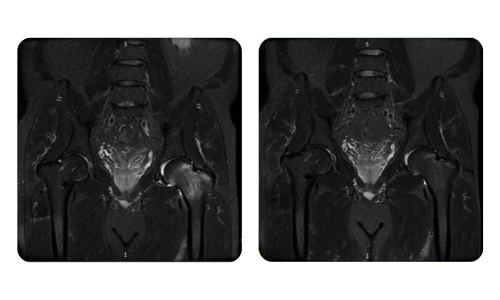

The progress of our patients, measured before and after hyperbaric therapy, reflects the efficiency and positive impact of the treatment. Discover documented results of hyperbaric therapy at Hyperbarium Oradea clinic, based on clinical evaluations and objective data that highlight significant improvements in various conditions.